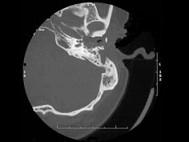

患者,李某,20岁,自幼右耳听力较差,其乳突CT摄片如图所示,可考虑为 ( )

答案: C